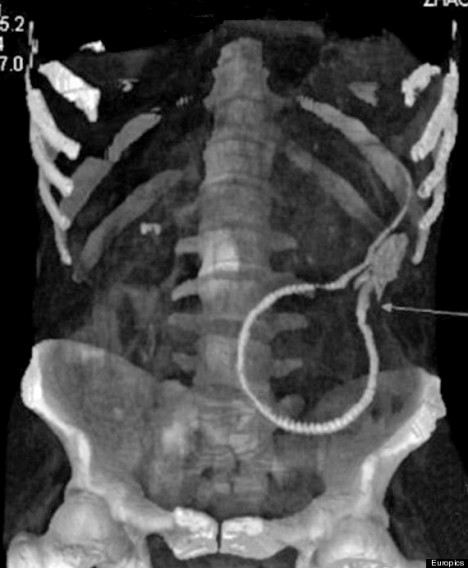

Eel

A man in China's southeastern Guangdong province admitted himself to a local hospital after he reportedly got a live eel stuck inside him. According to British tabloid The Sun, the man inserted the 20-inch-long Asian swamp eel into his anus after seeing it done in a porn movie, and he had to endure all-night surgery to have it extracted.